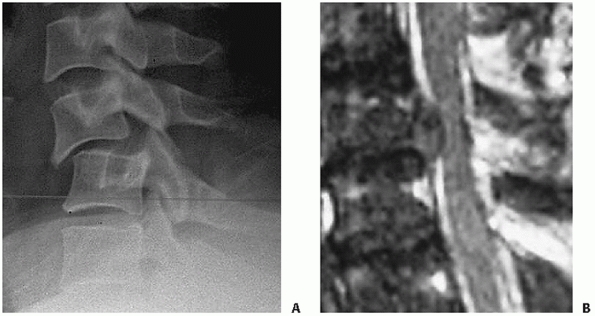

should be noted. Prevertebral swelling can be detected by assessing the

soft-tissue shadow thickness anterior to the vertebral bodies (Fig. 42-4).

If this measures more than seven mL in front of the C2-C3 disc space or

more than 21 mL at the C6-C7 disc space, there is a high likelihood of

a cervical spinal injury.167,223

Importantly, the absence of prevertebral (retropharyngeal) soft-tissue

swelling does not reliably rule out an occult cervical spine injury, as

its reported sensitivity is only 65%.129

and measured on the lateral view. The distance between the posterior

vertebral body tangent lines at the level of the disc space can be used

to measure the absolute distance in milliliters (Fig. 42-10). According to the work of White and Panjabi,248

3.5 mL of translational deformity is suggestive of mechanical

instability. Lateral translation, although much less common, can be

measured on the AP view by drawing longitudinal (vertical) lines along

the lateral masses.

that can be performed on the lateral view. While it might reflect the

axial stability of the anterior column, there are no specific criteria

on a critical percentage of vertebral body height loss. The anterior

and posterior vertebral body heights should be measured at the injured

and adjacent uninjured levels. The distances of the uninjured levels

should be averaged and the percentage height loss for the anterior and

posterior vertebral bodies calculated (Fig. 42-11).